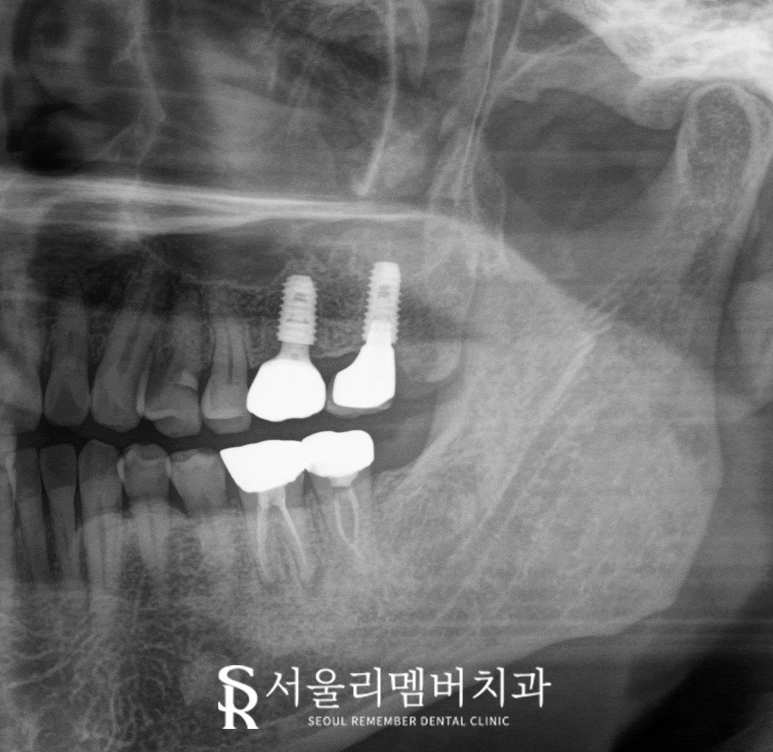

모든 진료가 끝났습니다.

신림역 치과 에서

금이 간 어금니를 빼고

그 자리에 임플란트를 심었으며

최종 보철까지 올린 모습을

보여드리겠습니다.

2025.05.20

임플란트는 자연치와 비슷한 기능을 하며

관리만 잘해준다면

반영구적으로 사용할 수 있습니다.

그렇기에 어금니같이 중요한 역할을

하는 부위에 적합하기도 합니다.